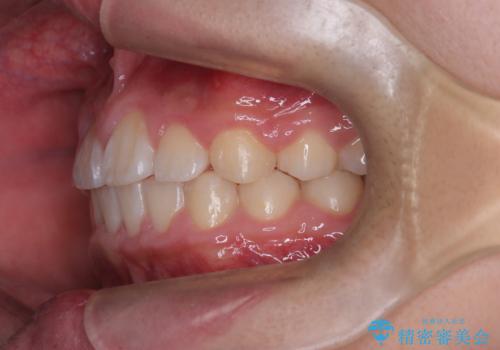

八重歯・歯並びのデコボコとディープバイトを改善した抜歯ワイヤー矯正症例

- 八重歯と咬み合わせを治したいを主訴にご来院された患者様です。

矯正の精密検査の結果上顎左右4番の計2本を抜歯し、審美性に配慮したワイヤー矯正装置(審美装置)を用いて治療を行いました。

八重歯などの歯列のデコボコが綺麗に改善され、患者様にも大変喜んでいただけました。また、咬み合わせが深い「ディープバイト」も併せて改善し、見た目だけでなく機能面でもバランスの取れた咬合を獲得しています。